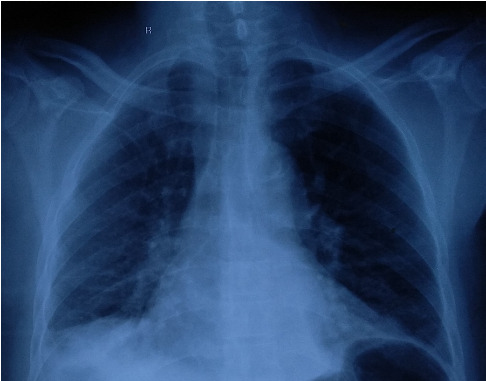

Background: Staphylococcal infection is a common bacterial disease with common clinical features. Untreated infection, especially in immunosenescence cases, can affect other organs. This can lead to multiorgan dysfunction and cause increased morbidity and mortality. Unlike commonly presented features of pneumonia, dissemination of infection can pose diagnostic and therapeutic enigma. Therefore, any such presentation in common clinical practice can yield a conundrum of diagnoses. Case Report: A 69-year-old elderly male presented to the Emergency Department with acute onset encephalopathy. Historically, cues were limited, and evaluation was negated for acute cerebrovascular event or seizure. Laboratory findings were suggestive of a severe sepsis. While clinical medicine workup and diagnostic dilemma were ongoing, possible sources of the sepsis were thoroughly sought including range of infectious causes. This patient's presentation was one of its kind: staphylococcal bacteremia seeding to cause pneumonia and unusual epidural abscess in due course of illness. Conclusion: The health outcome of the critically ill especially elderly patients depends mostly on the importance of clinical medicine to address the diagnostic enigma and virtue of supportive care delivered. Staphylococcus aureus infections are capable of developing distant infectious foci, as highlighted in this case, and that the clinician should be alert to this possibility. This particular case firmly posits an admonition for clinicians and the importance of clinical medicine for critical reasoning to improve the patient outcome.